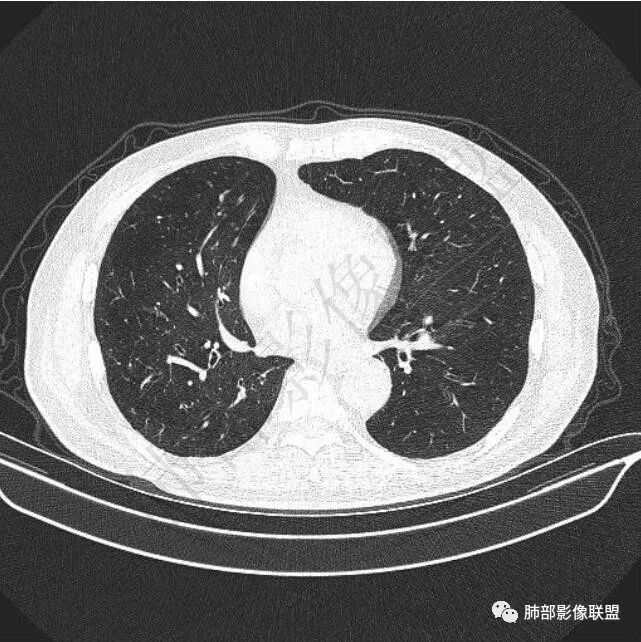

5年前鼻咽癌,2年前右肺上叶鳞癌手术史。

二..发现左肺上叶舌段实性密度小结节影,不规则略呈半环形,边界清楚,未见分叶、毛刺及磨玻璃晕。未见卫星病灶。

9个月后病灶明显增大,边缘较平直,部分膨隆,锁扣样外观,仍旧缺乏典型深分叶及张力,未见胸膜凹陷。

再1个多月后病灶继续增大,较明显不均匀强化,肺门一侧见低密度区。病灶边缘相对不清,可见毛刺。

三.病程脉络相当清楚,即病灶进行性增大,易想到新生物或转移瘤,但经验上分析增长速度显然太快,尤其是对于原发肺腺癌或者肺鳞癌而言,单发转移瘤也较少这样的进展速度。

四.单就影像而言,病灶肿瘤特征不够充分,恶性肿瘤病史,隐球菌等特殊感染确实不能排除。